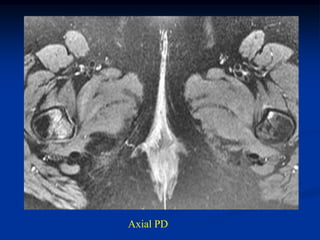

Case #1169.1                      Stress fractures

43 yr female on steroids for lupus with bilat hip pain for 6 months

Axial PD